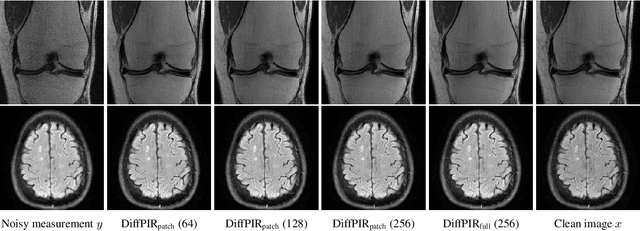

Abstract:Plug-and-play approaches to solving inverse problems such as restoration and super-resolution have recently benefited from Diffusion-based generative priors for natural as well as medical images. However, solutions often use the standard albeit computationally intensive route of training and inferring with the whole image on the diffusion prior. While patch-based approaches to evaluating diffusion priors in plug-and-play methods have received some interest, they remain an open area of study. In this work, we explore the feasibility of the usage of patches for training and inference of a diffusion prior on MRI images. We explore the minor adaptation necessary for artifact avoidance, the performance and the efficiency of memory usage of patch-based methods as well as the adaptability of whole image training to patch-based evaluation - evaluating across multiple plug-and-play methods, tasks and datasets.